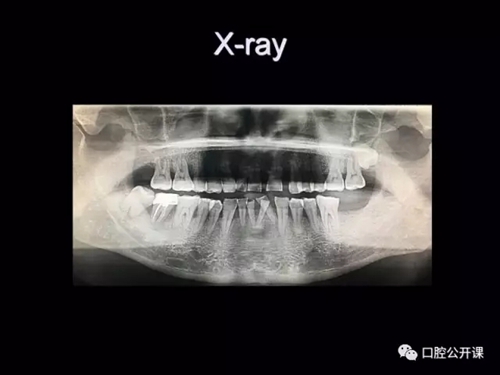

一例廣泛型侵襲性牙周炎5年臨床追蹤下

楊淑銀醫(yī)師用他的一例侵襲性牙周炎五年臨床病例追蹤來(lái)縮影一個(gè)青年牙周醫(yī)師的成長(zhǎng)之路,帶我們一起探索看似平凡枯燥的牙周基礎(chǔ)治療到底有怎樣的重要性?